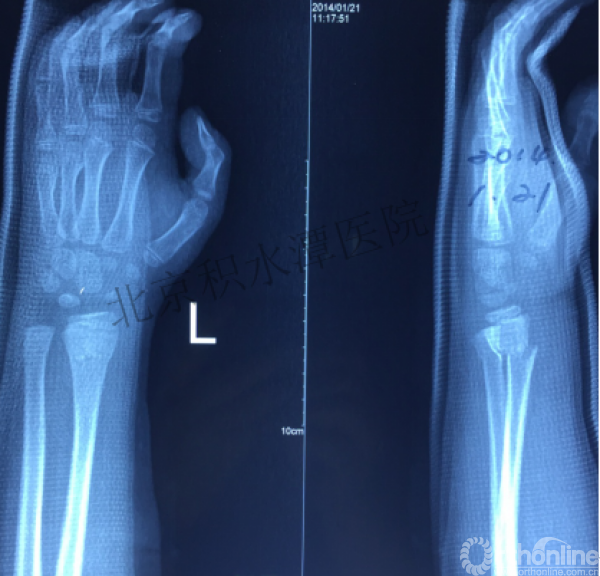

病例分享六

7岁、男孩,桡骨远端骨折

原始损伤片

手法整复后 - 45分钟!

伤后4天复查

伤后30天!

医生的处理方法!——医生终于没有坚持自己的原则!

伤后40天—切开复位内固定!

伤后18个月

如何面对?

心情之压抑无以言表!

手术历时近 5小时!心情之压抑无以言表!因为当时的经治医生是他们的进修生!感觉是他们的失职甚至渎职!

唯一可以肯定—预后不佳!郭教授是党员!是无神论者!但是很诡异的事情:手术中发生—C形臂看不清!拍片条件总是调节不好!手术器械换了三套!内固定钢板总不合适!

术后15月,虽然家长满意了,但是他们医生不满意!